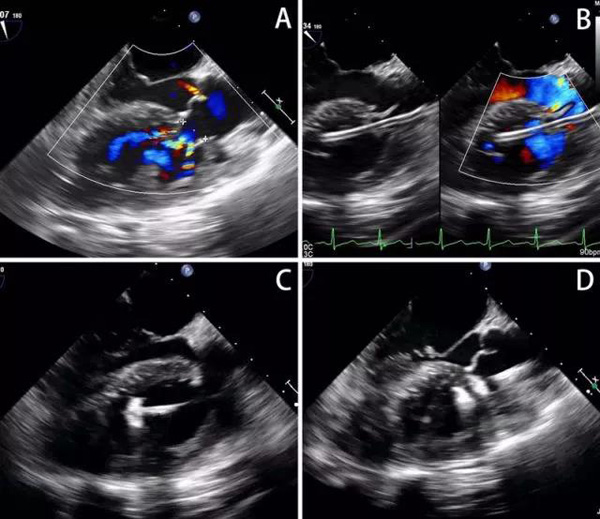

心外科联合超声诊疗科、麻醉科共同经过审慎讨论后,决定在控制患者心衰后,用最新的外科介入技术救治该患者。什么是外科介入?这是一种在单纯超声引导下的微创导管治疗,术中经皮穿刺或经胸部小切口,将一根输送鞘管插至主动脉窦瘤破口,用特制的“铆钉”封堵住窦瘤破裂,操作过程不需要体外循环,不输血,医患双方均不接触X线。

由于该患者窦瘤破口多发,医护人员们在术前专门订制了更匹配的封堵器。手术由李红昕主任主“刀”,在超声理疗科主任郭文彬的超声引导下,不做任何切口,仅穿刺大腿血管,把一根输送鞘管经主动脉全长,插至窦瘤破口,将特制的封堵器铆定在窦瘤破口处,成功堵住了“决堤”的主动脉。手术仅历时46分钟,患者重获新生。